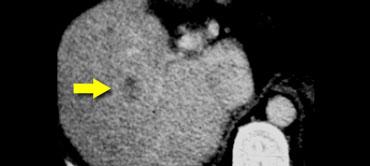

Ca lâm sàng bên trái minh họa mức độ khó khăn trong việc phát hiện ung thư đường mật.

Chỉ trên các hình ảnh thì muộn, 8-10 phút sau tiêm thuốc cản quang, mới thấy được tổn thương tương đối tăng tỷ trọng. Đây chính là thành phần xơ của khối u.